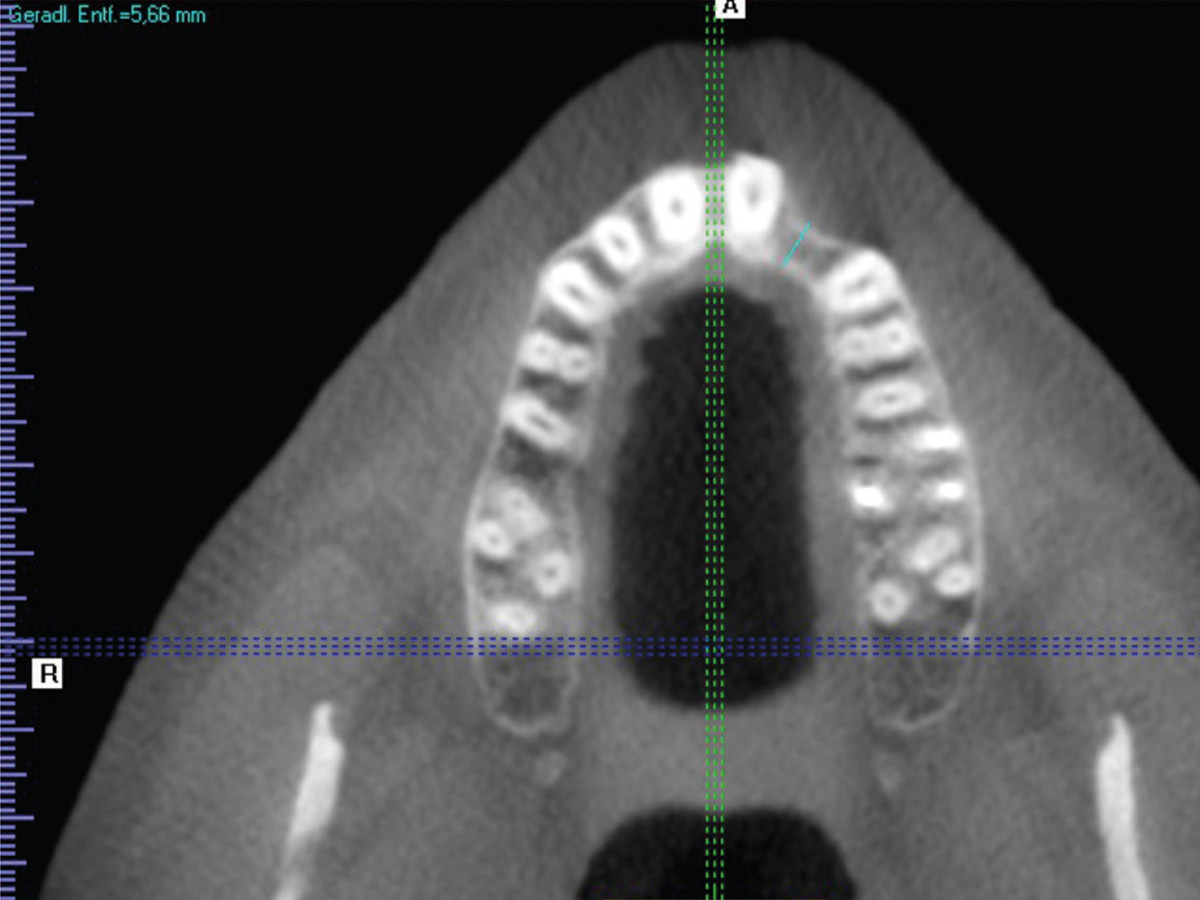

Abbildung 2

Der Defekt im DVT, die Restknochenbreite beträgt 5,6 mm.